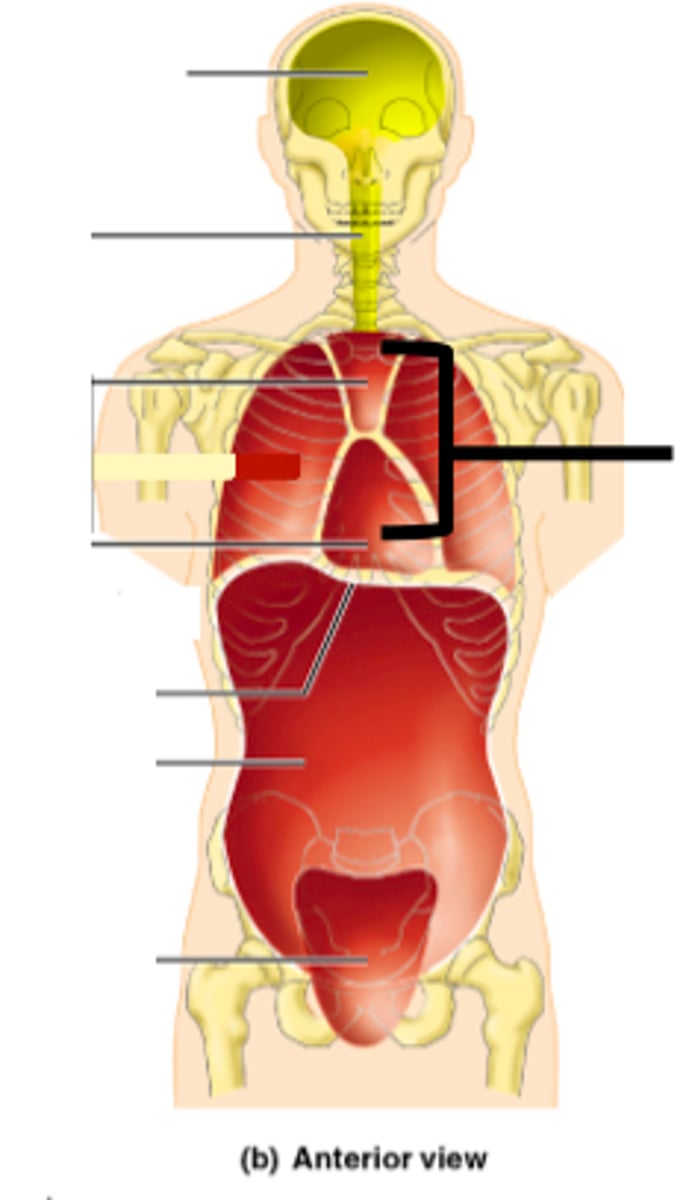

Precordium

The area on the anterior chest overlying the heart and great vessels

Mediastinum

The space located between the lungs where the heart is found

Anatomy of the Heart